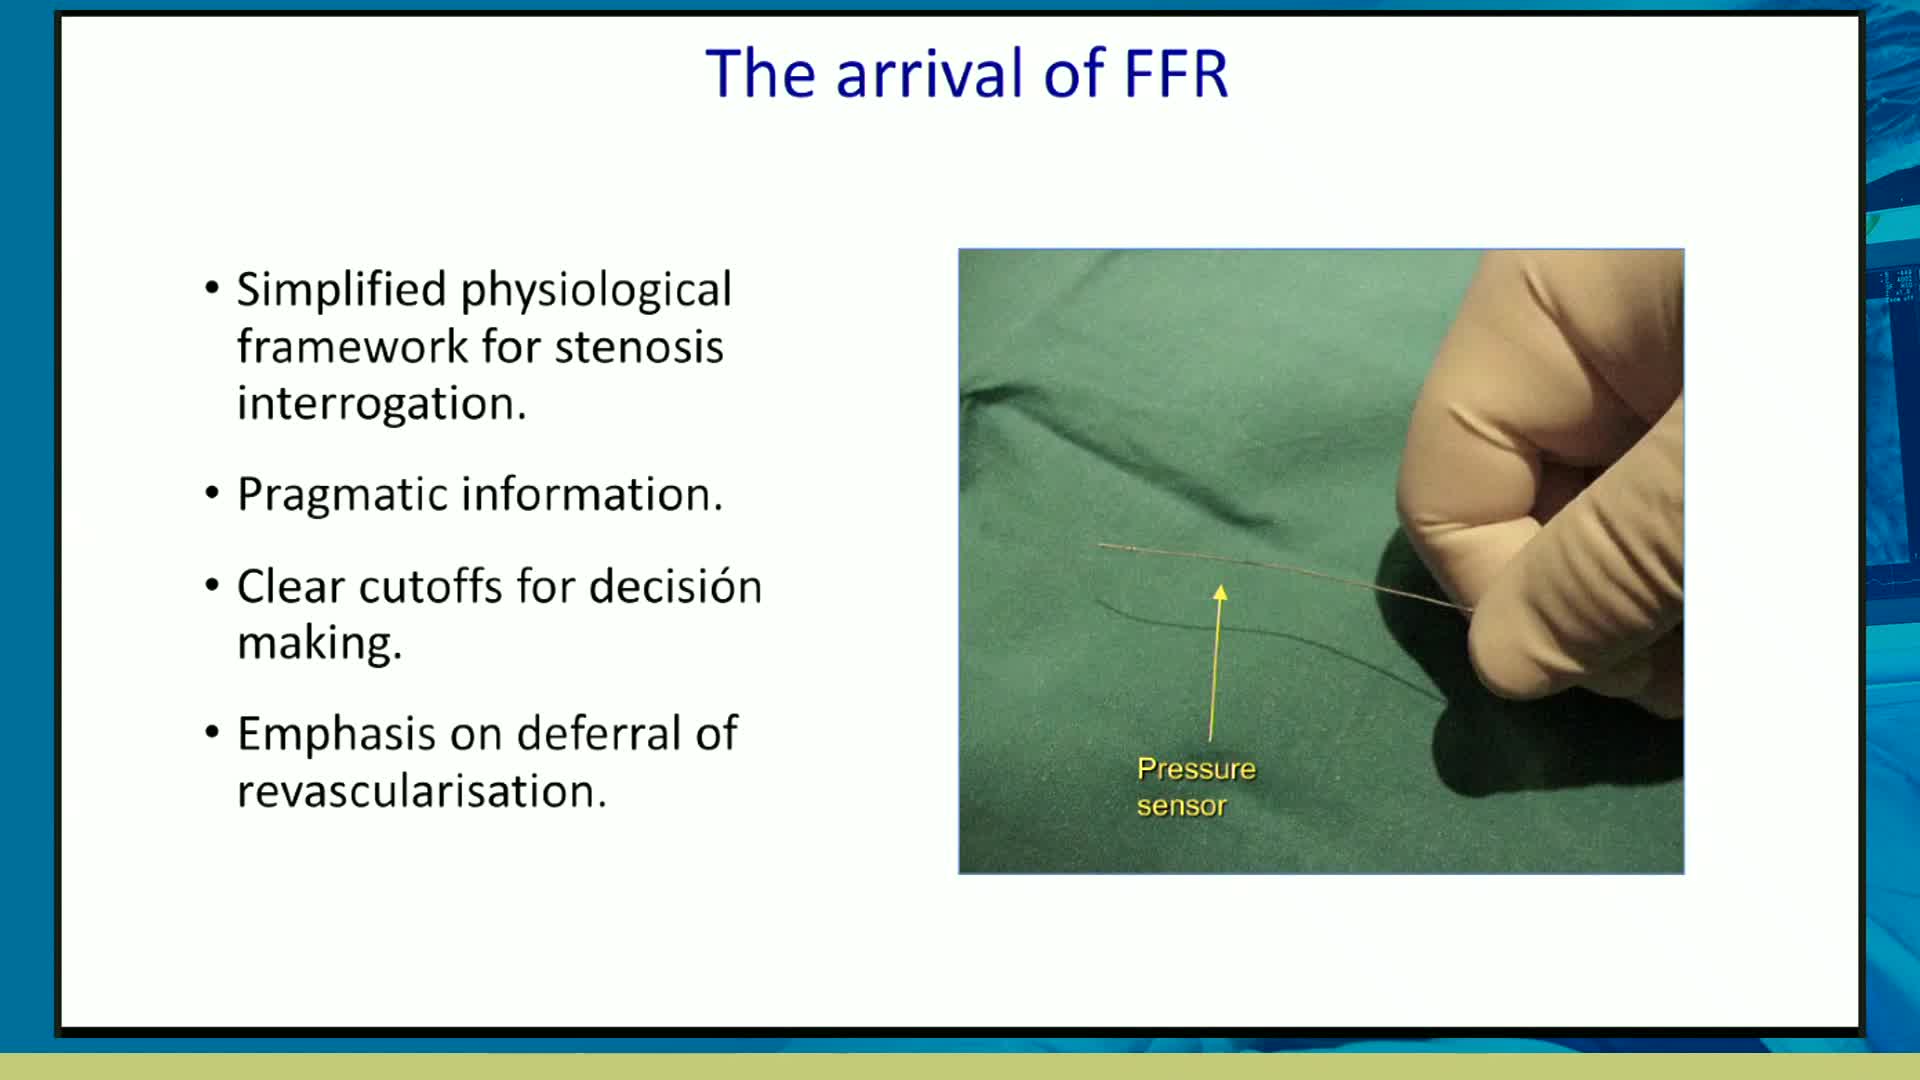

Understanding mechanisms of regulation of resting and hyperaemic blood flow, across single and serial stenoses

20 year overview of clinical trial data to support the use of coronary physiology in revascularisation decision-making

How to perform iFR and FFR, and best-practice measurement tips and tricks - Dr Ricardo Petraco